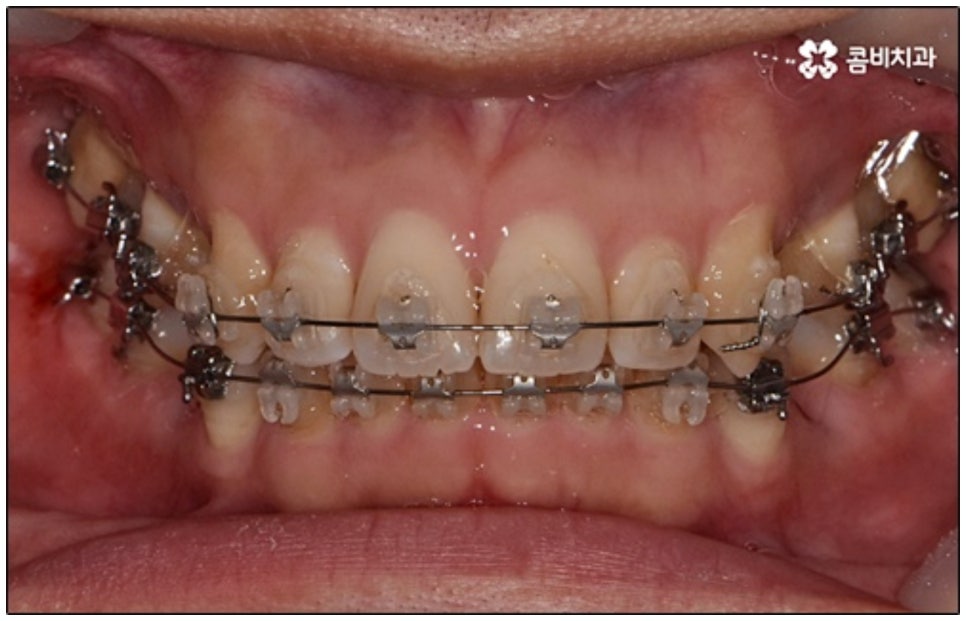

요즘 가장 많이 쓰이는 것은 클리피씨교정 장치로, 브라켓에 자체적으로 여닫을 수 있는 클립(뚜껑)이 있어 보다 손쉽게 와이어를 장착하거나 제거할 수 있어요. 이와 같은 자가 결찰 방식을 이용하게 되면 미세 철사로 일일이 와이어를 잡아주지 않아도 되기 때문에 장치로 인한 불편함이나 통증이 줄어들 수 있는데요. 뿐만 아니라 관리를 위해 치과에 내원하여 진행 상황에 맞게 새로운 와이어로 교체하고 교정력을 걸어주는 데 걸리는 시간 역시 단축되며, 상황에 따라 내원 횟수 자체를 줄여줄 수도 있어 방문 시간을 내는 것이 자유롭지 않은 군인분들이나 직장인분들도 치료할 수 있어요.

또한 클리피씨교정 장치는 심미성이 높기 때문에 많은 분들이 선호하고 있는데요. 클립이 달린 세라믹 (cilppyC-Ceramic의 약자) 이라는 뜻을 가진 이름에서 알 수 있듯이 클리피씨교정 장치는 브라켓 소재가 치아 색상과 비슷하여 눈에 잘 띄지 않으며 내구성이 좋고 크게 변색 되지 않는다는 장점을 가지고 있어요.

말씀드린 것과 같은 다양한 이점들이 있기 때문에 현재 본원의 교정 환자분들은 대부분 클리피씨교정 장치를 이용하여 치료를 진행하고 있습니다. 사진 역시 돌출입 교정을 위해 발치 후 클리피씨교정 장치를 이용하신 환자분의 케이스인데 시간이 지날수록 점차 앞니가 자연스럽게 들어가고 위아래 교합이 정확하게 맞아가는 것을 확인하실 수 있을 거예요.